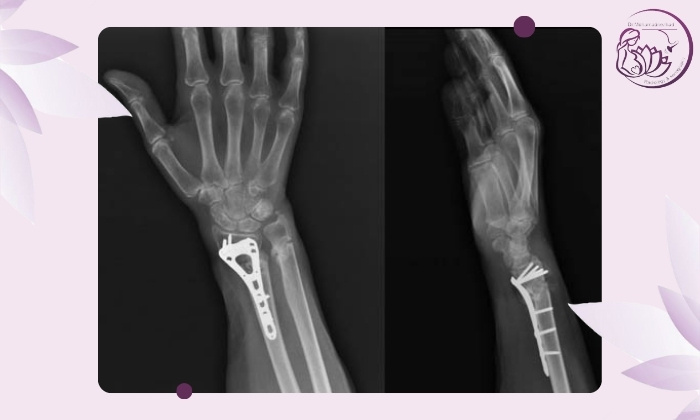

تصویربرداری با رادیوگرافی (X-ray)

رایج‌ترین ابزار تشخیص است. پزشک با مقایسه عکس‌های جدید با تصاویر قبلی موارد زیر را ارزیابی می‌کند:

وجود شکاف بین قطعات استخوان (عدم اتصال)

نبود نشانه‌های تشکیل کال استخوانی (Callus)

حرکتی بودن شکستگی در محل اتصال

در موارد شک‌برانگیز عکس‌ها در دو زاویه گرفته می‌شود تا وضوح بیشتری داشته باشند. چنانچه قصد انجام رادیولوژی در جردن را دارید می‌توانید به مرکز تصویربرداری دکتر محمدنژاد مراجعه کنید.

فیکساتور داخلی (Internal Fixation)

استفاده از پلاک، پیچ، میله یا پین برای ثابت نگه داشتن استخوان

ایجاد محیط پایدار برای ترمیم